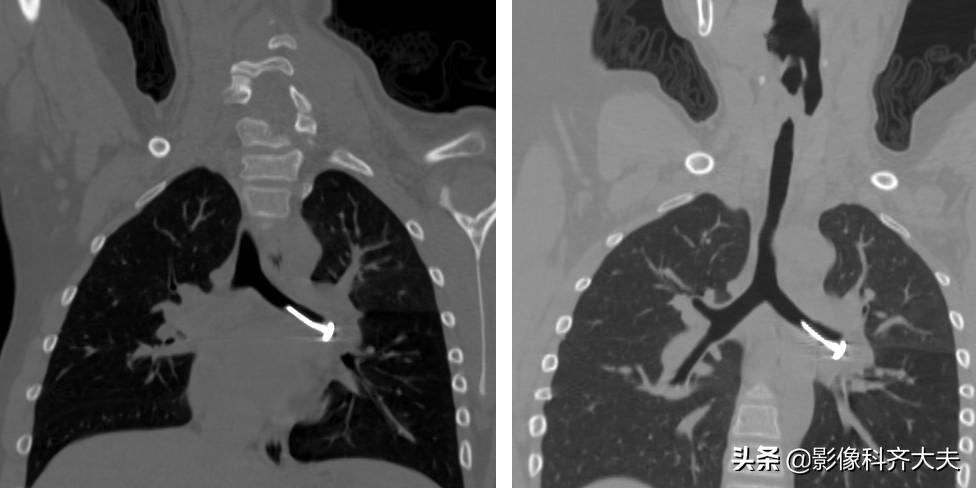

病例6、病史:女,两岁,吃花生时喝水引起呛咳。

轴位显示左侧支气管疑似异物,红色箭头。

冠状位重建清晰显示左侧支气管异物,红色箭头所示。

最小密度投影显示的更加清楚。

这是CPR(曲面重建),即单独对左侧支气管进行重建显影,清晰显示异物。

曲面重建后在进行最小密度投影重建,异物显示的更加清晰。